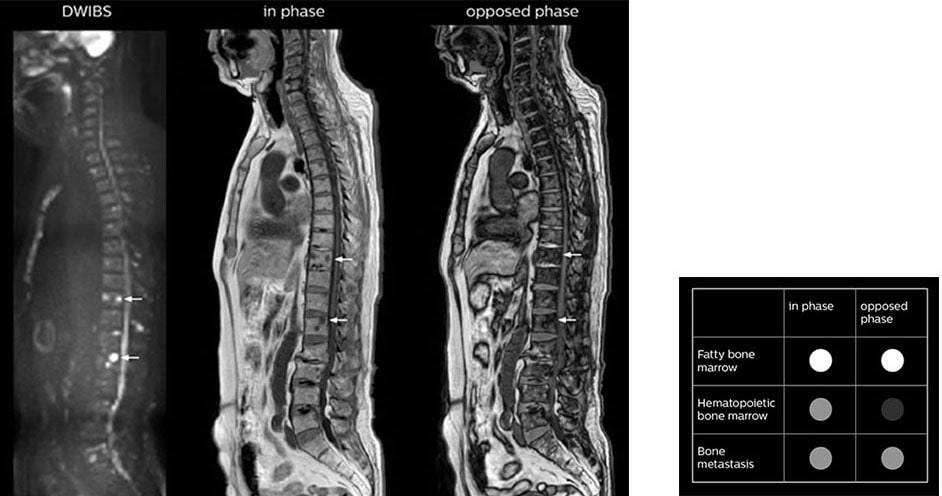

“mDIXON FFE allows us to quickly get information we need to assess the presence of fat. That gives us more information when we need to diagnose bone lesions, and when we are asked to judge fat-containing lesions such as hepatocellular or renal carcinoma,” Dr. Nobusawa says. “The mDIXON fat images can help us to differentiate fatty bone marrow from bone lesions. This is especially useful in elderly people, who tend to have fattier bone marrow. The water images provide a high signal-to-noise ratio in the intestinal canal, which is valuable for visualizing lesions in the colon,” he says.

Kawasaki Sawai Hospital’s whole body protocol also includes an mDIXON FFE sequence. Because mDIXON provides images for four contrast types – water only, fat only, in-phase and out-of-phase – from a single acquisition, it is useful in many ways.

“In-phase and out-phase sagittal T1-weighted FFE images help us to visualize and further characterize bone lesions such as metastasis and bone-marrow hyperplasia that have high signal on DWI. These images are also used throughout radiotherapy, to monitor changes in the fatty bone marrow.”